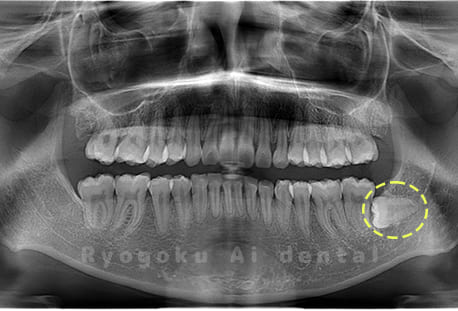

斜めに生えている親知らず

親知らずが斜めに生えて隣の歯にぶつかって圧迫してしまうタイプです。

このタイプが最も多いです。このタイプは虫歯になりやすいだけでなく、隣の歯を圧迫し、咬み合わせや歯並びに影響が出る場合もあるので抜歯をおすすめします。